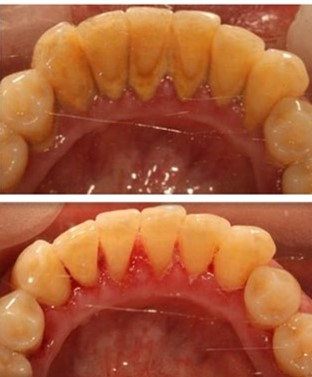

洗完牙即刻拍的照片,患者自己觉得牙白了。

这位患者也觉得牙变白了,其实仅仅是脏东西没了